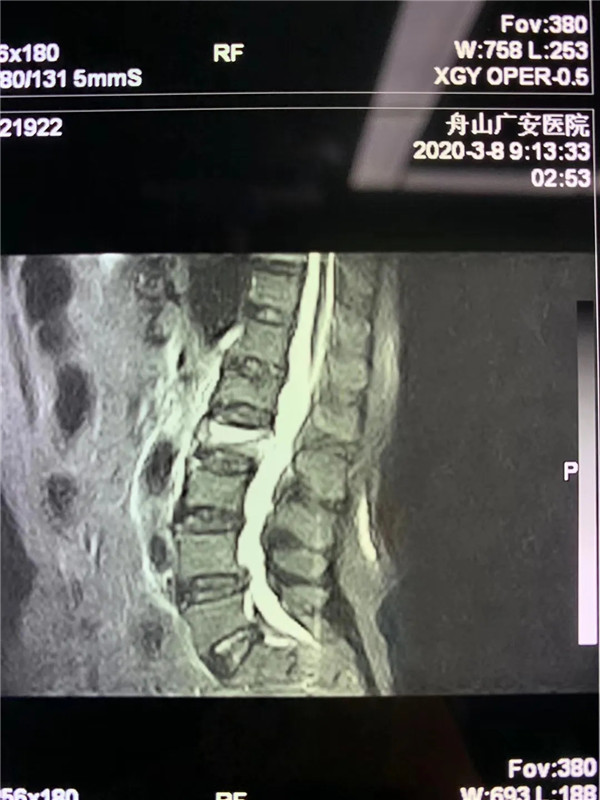

經(jīng)過仔細問診和查體后,初步診斷曹阿姨是椎體壓縮骨折了,在完善胸腰椎的MRI線檢查后,也證實了推斷。在與曹阿姨及家屬充分溝通后,戈才華主任為曹阿姨實施了微創(chuàng)手術,很快為其緩解了疼痛。

(MRI顯示椎體壓縮性骨折)